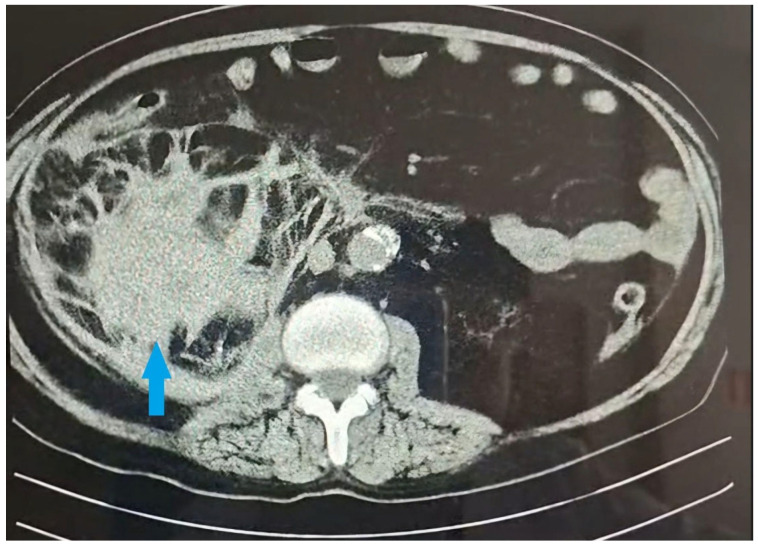

Background and Clinical Significance: Spontaneous renal hematoma, also known as Wunderlich syndrome (WS), is a rare disease characterized by the acute onset of spontaneous renal hemorrhage into the subcapsular, perirenal, and/or pararenal spaces without a history of prior trauma. WS can be a life-threatening condition due to hemorrhagic shock; consequently, prompt diagnosis and a therapeutic approach are essential for favorable outcomes. Treatment ranges from conservative management to surgical intervention. The most common etiologies are neoplasms and vascular diseases, but WS can also be observed in patients undergoing hemodialysis. In patients with end-stage renal disease (ESRD), especially those on hemodialysis, acquired cystic kidney disease and renal cell carcinoma are among the primary causes of WS. Although less common, WS can develop in dialysis patients even in the absence of traditional (primary) risk factors. In general, patients with chronic kidney disease (CKD) have a paradoxical hemostatic profile, likely explaining their higher tendency to bleed, so WS can occur without existing predisposing factors. The multifactorial pathogenesis in these patients includes functional platelet abnormalities, intimal arterial fibrosis, chronic inflammation, and oxidative stress associated with ESRD. The use of hemodialysis-related antithrombotic medications could serve as another contributing factor increasing the risk of bleeding. Case Presentation: We present a case report of a 62-year-old male on chronic dialysis who developed sudden right-sided lumbar pain and hematuria during dialysis without evidence of prior trauma. Imaging revealed a large subcapsular hematoma of the right kidney. Further investigations did not reveal additional risk factors in this instance; however, his routinely used hemodialysis-related antithrombotic medications were potentially a contributing factor. Despite conservative treatment, his condition worsened, and the hematoma enlarged, requiring emergency nephrectomy. Postoperatively, his condition gradually improved. Conclusions: This case highlights the importance of considering WS in hemodialysis patients, even without the presence of traditional risk factors, as well as including WS in the differential diagnosis of acute abdominal pain.